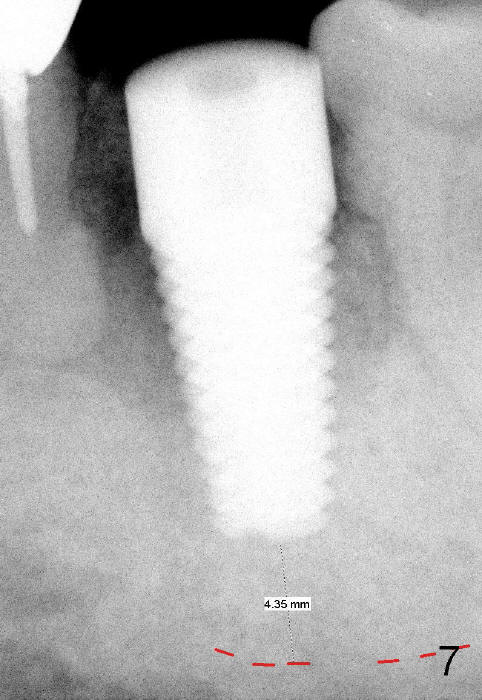

Prior to implant placement (Fig.7,9: 7x17 mm with insertion torque 40 Ncm), a mixture of autogenous bone (Fig.8 red particles) and demineralized cortical allograft (white granules) is packed against defective socket walls, particularly apically. It leaves a space in the middle of the socket for implant insertion later on. In this case, the buccal wall around the apex, corresponding to the fistula (Fig.9 >) is severely destroyed, whereas the crestal portion is more or less intact. Three months later, the implant appears yet to osteointegrate (Fig.10), while the fistula disappears (Fig.11). The large implant does not look too overengineered over the alveolus (Fig.12 (lingual view). In fact, the implant has mild mobility. How to fix it?